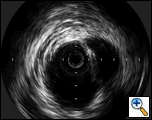

| Figure 4: “Completion”-IVUS examination showing exclusion if the proximal descending aorta. |

concerns about myocardial contusion. After lowering the systolic blood pressure to 100 mmHg, the stent graft was deployed precisely distal to the left common carotid artery. Small boluses of contrast were administered during deployment to confirm device position relative to the left carotid artery. A completion aortogram confirmed adequate exclusion of the transected area and no evidence of an endoleak was identified. A completion IVUS exam was performed, showing complete apposition of the device to the aortic wall circumference (Figure 4). Subsequently, the catheters and the wire were removed from the left groin, and the left common femoral artery is repaired under direct vision. The patient was found to have bounding distal pulses and was neurologically intact after the procedure. The pulses of the left arm were detectable with Doppler. Although the systolic blood pressure in the left arm decreased by 30 mm Hg, the patient did not demonstrate any ischemia or claudication symptoms.